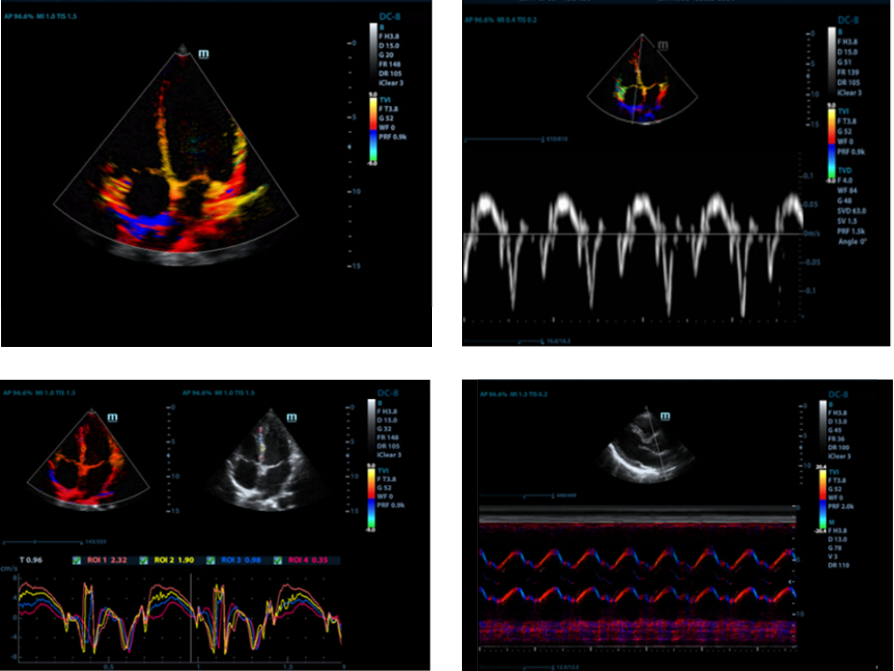

Tissue Doppler Imaging with Quantitative Analysis (TDI and TDI-QA)

Supported by MindrayŌĆÖs unique 3T technology with single crystal, the M7 premium significantly improves the performance of Tissue Doppler Imaging. With the added quantitative analysis package with comprehensive parameter outputs such as velocity, strain and strain rate, the TDI-QA performs with ease at the bedside.